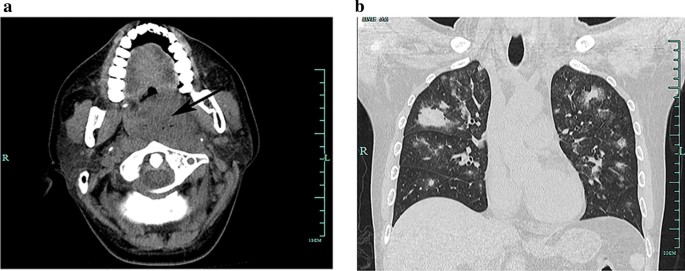

A 33-year old man without any medical history was admitted to our hospital because of a sore throat and dry cough for 2 months. He also presented recurrent fever and weight loss of more than 10% in the meantime. The patient was admitted to the infectious department of our hospital. On admission, the physical examination found the left tonsil being grade II swollen, with pus coating the surface. He breathed at 25–30 times per minute; no audible rale was heard on the auscultation. The computed tomography (CT) found an oval soft tissue mass in the oropharyngeal cavity, with some gas shadows in the lesion (Fig. 1a). The pulmonary CT scan found multiple lesions distributed among both lungs. Among them, most appeared as ground-glass subsolid nodules, some showed consolidation, and the lesion in the right upper lobe showed a mass-like appearance (Fig. 1b). The C-reactive protein was 42.37 mg/l (normal range: 0–8 mg/l), the procalcitonin was 0.09 ng/ml (normal range: 0–0.5 ng/ml), the white blood cells count was 4.5 × 10 E9/l (normal range: 4.0–10.0 × 10 E9/l), and the serum lactate dehydrogenase (LDH) was 718 U/l (normal range: 109–245 U/l). Candida albicans were detected by throat swab. The patient was initially diagnosed with the tonsil abscess and pneumonia, which were possibly due to complex infection, including the bacterial and fungal infection. The patient received combined treatment with meropenem, linezolid, and caspofungin for more than a week. However, the initial treatment showed no effect. The results of a series of tests came out, showing that (1,3)-beta-d-glucan (G test) and galactomannan (GM test), sputum culture, acid-fast smear, gomori methenamine silver stain, and respiratory virus screening were all negative. Then the otolaryngologist was consulted, and surgical debridement was performed. During the surgery, a lot of hyperplastic and necrotic tissues were found in the oropharyngeal cavity, and the left tonsil was grade II swollen and festered. The pus and necrotic tissue were debrided, and the left tonsil was taken off. The histopathology found that the tonsil was absent of normal structure, mainly composed of medium-sized cells, with abundant cytoplasm, and the mitotic images can be seen. On immunohistochemical staining, these atypical cells were positive for CD-2, CD3, CD30, CD56, c-Myc, TIA-1, and granzyme B, while CD5, CD10, CD20, CD21, CD23, Bcl-2, Bcl-6, MUM1, PAX-5, CyclinD1, and ALK were negative. Epsteine Barr virus encoded RNA (EBER) in situ hybridization was strongly and diffusely positive in the cells. The Ki-67 proliferation index showed 80% nuclear staining (Fig. 2). The serum EBV DNA level was 1.72 × 10 E6 copies/ml in the test after surgery. These findings were consistent with ENKL. While the patient got refractory hypoxemia immediately upon arrival in the ICU after surgery. The bedside chest radiograph showed bilateral diffuse opacities in the lung (Fig. 3), and ARDS was diagnosed. The CRP increased to 96.16 mg/l, and the PCT increased to 1.09 ng/ml. We continued the experimental anti-infection therapy of meropenem, linezolid, and caspofungin. While following sputum cultures were still negative. Although the CRP and PCT declined gradually to 55.70 mg/l and 0.32 ng/ml respectively, the hypoxemia didn’t resolve. The patient got deterioration rapidly, with the LDH surging to 1660 U/l. He died of ARDS on the 5th day after surgery.

CT images of the neck and the chest on admission. a The arrow shows an oval soft tissue mass was in the oropharyngeal cavity, about 3 cm in diameter, with some gas shadows in the lesion. b Chest CT revealed multiple lesions among both lungs. Most of them appeared as ground-glass subsolid nodules, some showed consolidation, and the lesion in the right upper lobe showed a mass-like appearance